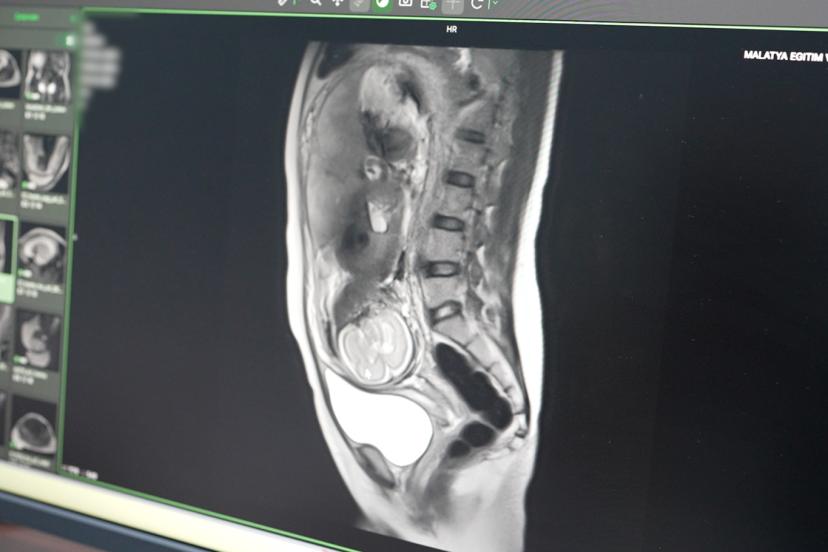

Hastanede uygulanmaya başlayan bir diğer özellikli incelemenin fetal MR olduğunu belirten Petik, anne karnındaki bebeğin gelişim bozuklukları, doğumsal anomaliler ve riskli durumlarının detaylı şekilde değerlendirilebildiğini ifade etti. Fetal MR sayesinde kadın hastalıkları ve doğum uzmanlarının tanı süreçlerinin daha güçlü hale geleceğini vurgulayan Petik, doğum öncesi alınacak tedbirlerin de bu sayede daha doğru planlanabileceğini söyledi.